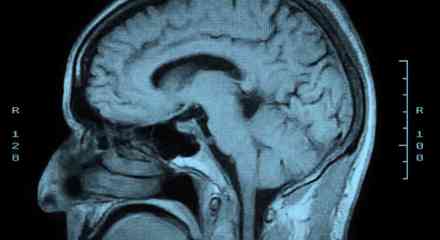

When I was in Boston, I had a patient with a brain tumor and two adult sons. She had a malignant, progressive brain tumor and had been unresponsive for months. Her prognosis was poor. One son, I’ll call him Peter, thought she would have wanted to be DNR/DNI: if her heart stops, if her breathing … Continue reading →